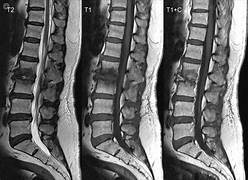

Galería Salud

Explora nuestro enfoque holístico para el bienestar de la espalda.